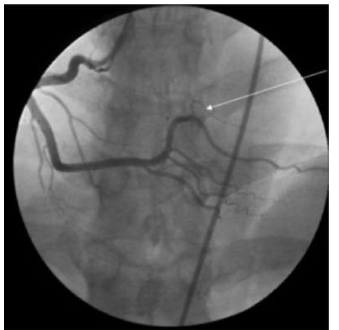

Em pacientes com infarto com supara de ST inferior, com oclusão da coronária direita e seus ramos, encontramos

com certa frequência bloqueios avançados.

Qual é a artéria assinalada na seguinte figura, considerando essa incidência oblíqua anterior esquerda?